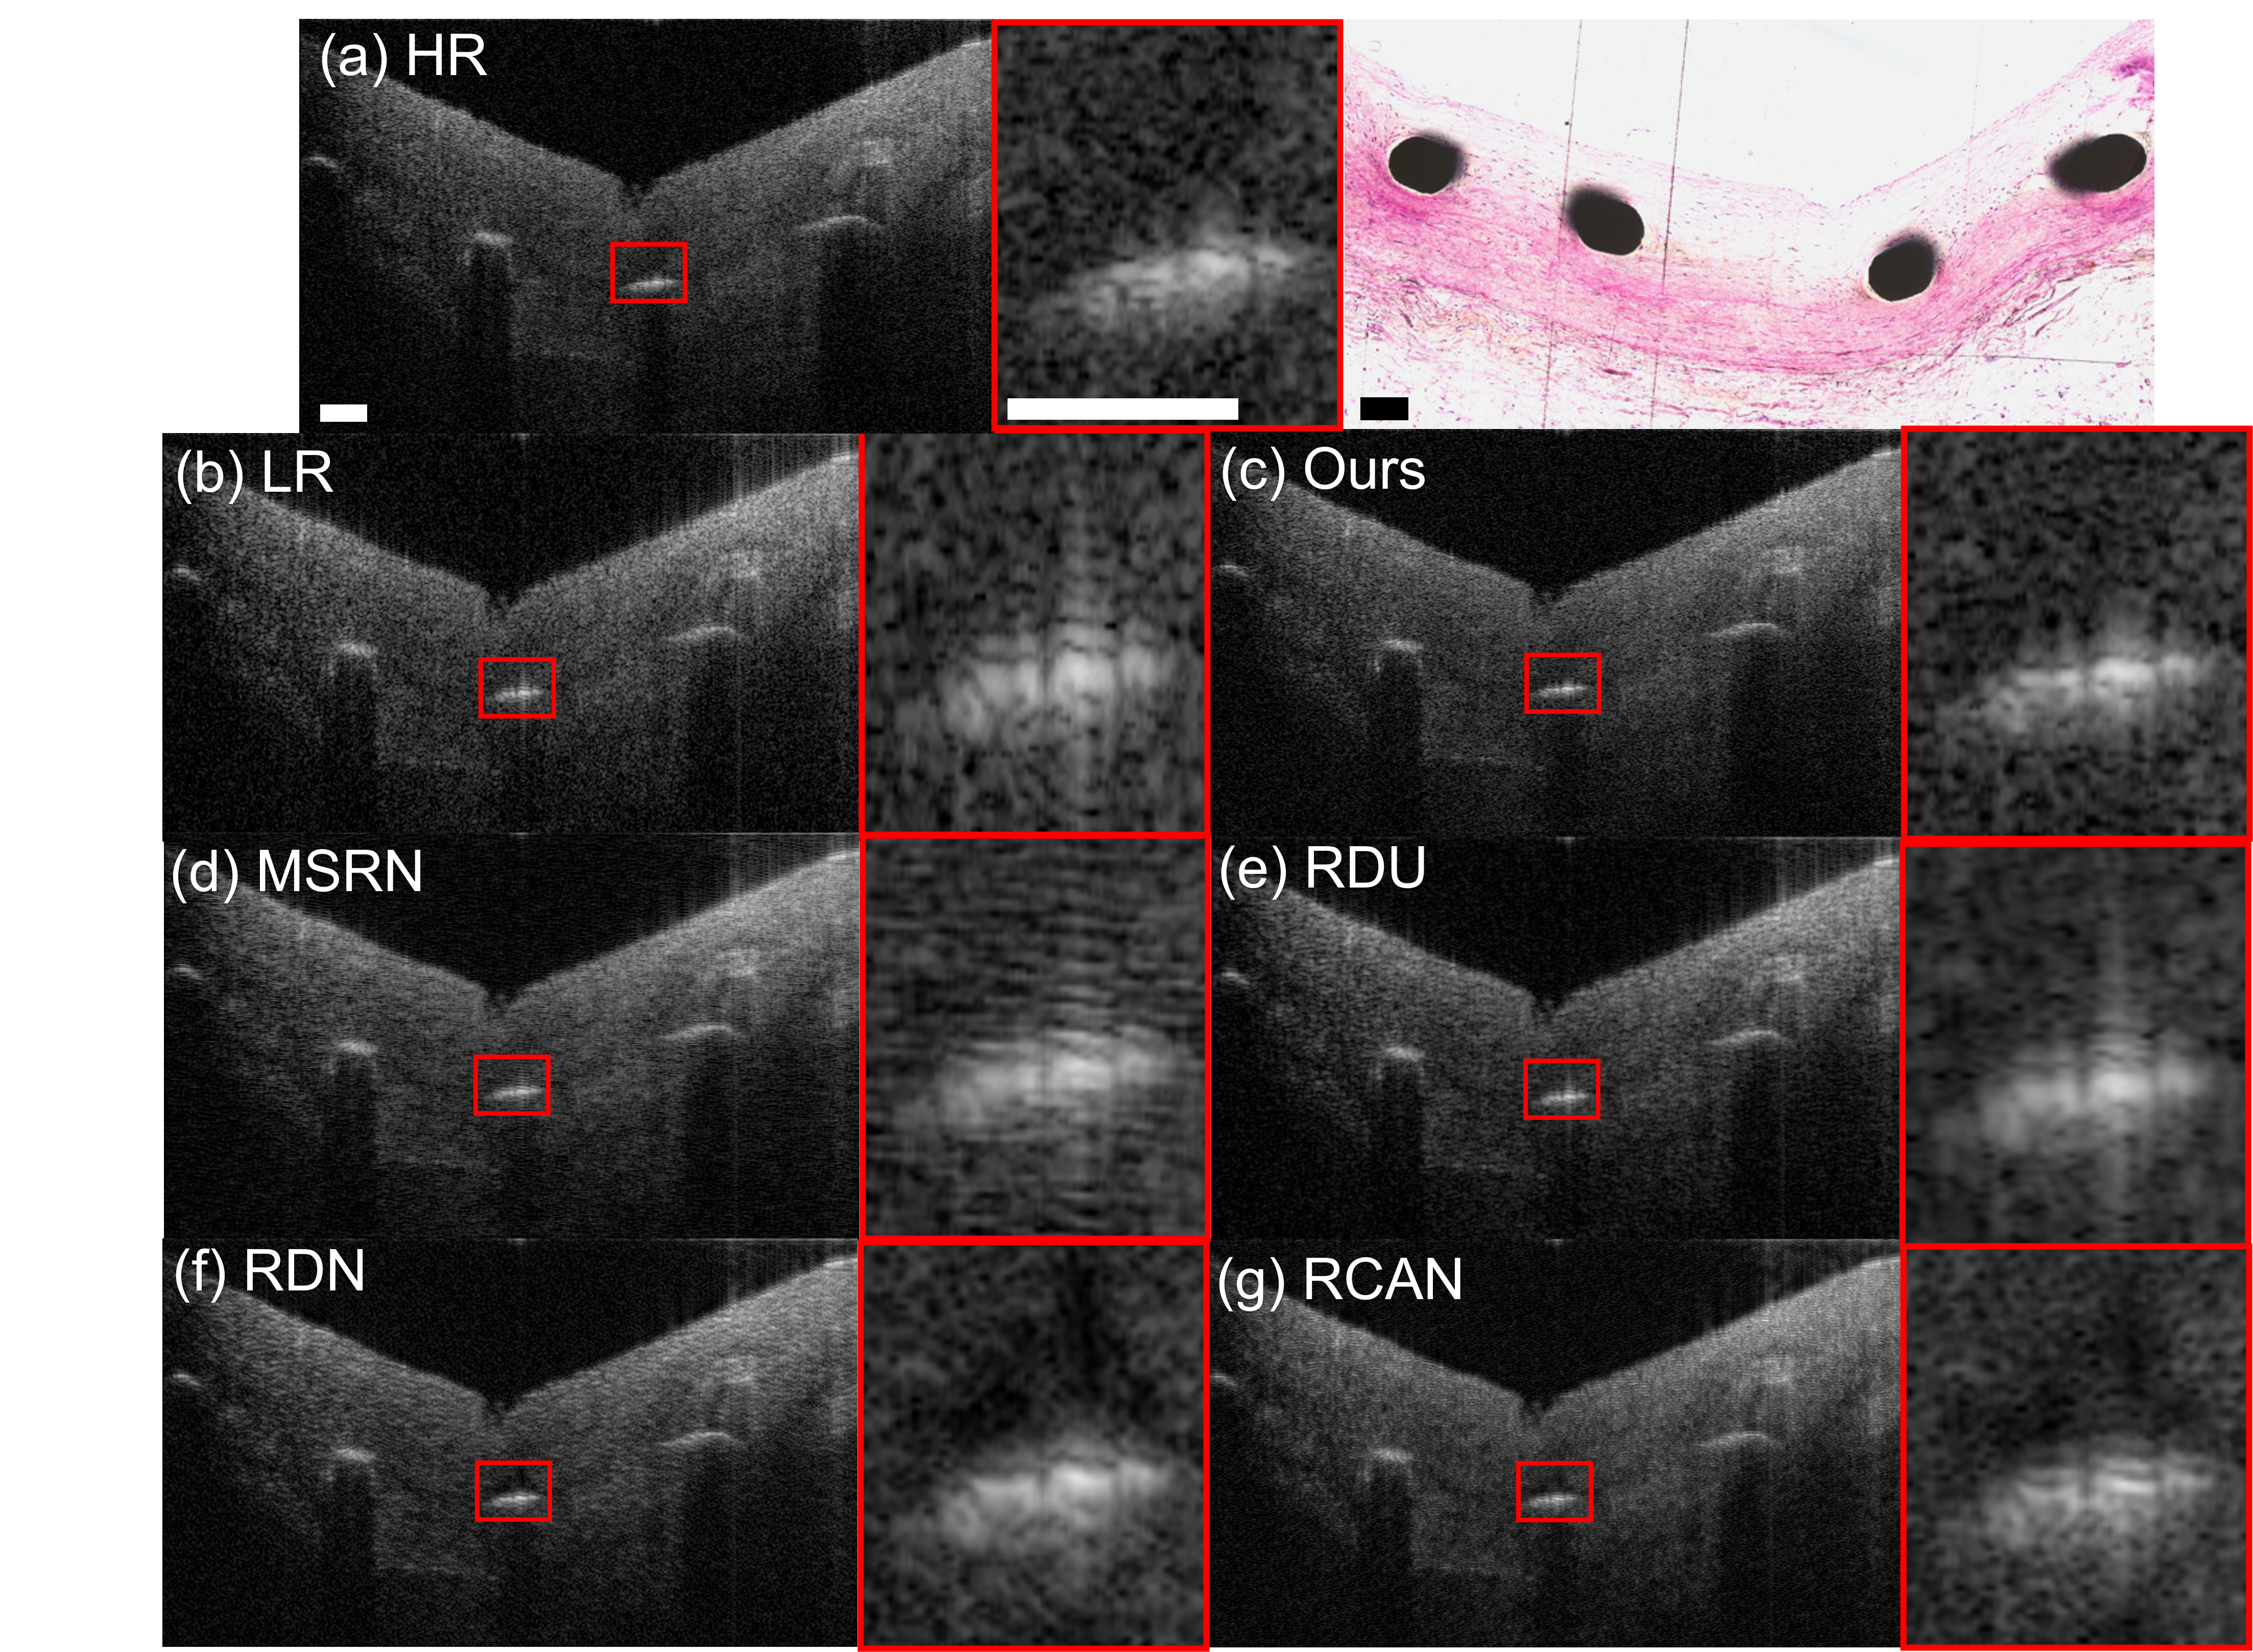

In Fig 4, a case of super-resolving an LR OCT image of a stent within the coronary artery is demonstrated. Coronary stent placement is an established treatment for CAD [33]. Imaging microstructures and tissues adjacent to stent struts are crucial in the clinic. It is critical to provide accurate morphological information on interactions between the stent and the vessel wall, for the purpose of evaluating the placement as well as the biocompatibility of the stent. The edges of the stent are considered to be high-frequency information in the OCT images, which are challenging to reconstruct for previous DL algorithms. As shown in Fig 4, previous DL algorithms generate blurred edges of the stent. Moreover, existing DL algorithms lead to artifacts on the interaction between the stent and tissue, as shown in Fig 4 (e), (f), (g). With our frequency-aware model, the edges of the stent are resolved with detailed information that is similar to that of the HR image.

In Fig 5, we demonstrate a case of super-resolving an LR OCT image of suspicious accumulation of macrophages. Macrophages play a critical role in both the development and rupture of atherosclerotic plaques [34], which are thus important for the diagnosis of CAD. OCT has been demonstrated to be a viable technique for visualizing the accumulation of macrophages in the human coronary artery. Macrophages appear as ’bright spots’ in OCT images [35], which are high-frequency information due to their sharp contrast with neighboring tissues. As shown in Fig 5, previous DL algorithms generate SR images with blurred macrophages, which will deteriorate the clinical diagnosis procedures. In contrast, our frequency-aware framework generates SR OCT images with clear macrophages. Thus, our frequency-aware model is capable of providing SR OCT images for human coronary samples with clinical meaningness.